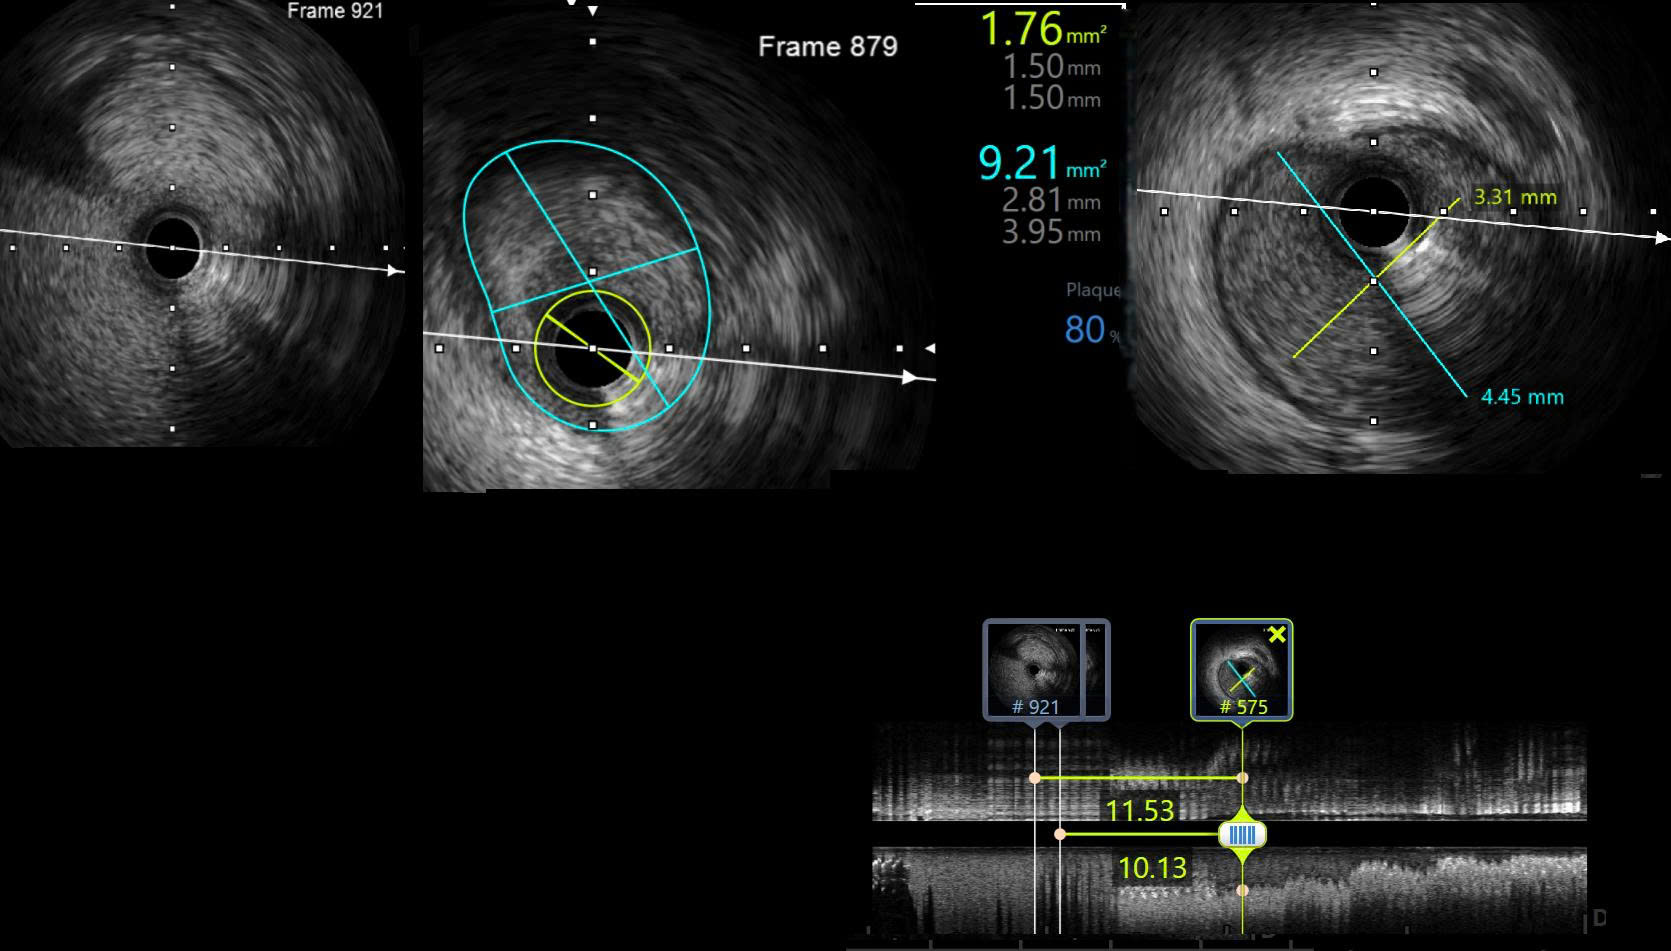

DSA and IVUS pre-intervention showed lesion located from proximal LAD to the ostium with the length of 12 mm, distal reference vessel diameter of 3.3 mm, vessel diameter of 4.4 mm. The lesion had an area of 1.76 mm2 with plaque burden of 80 %.